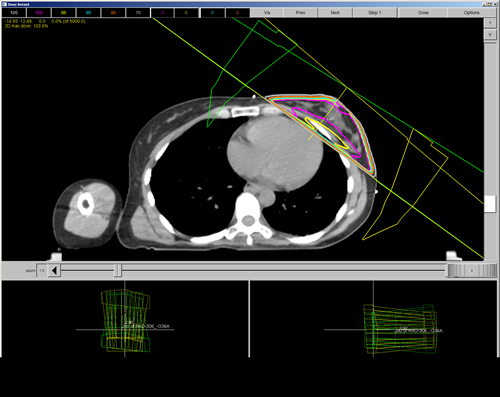

The isodose curves below could be improved by weighting one of the laterals more.